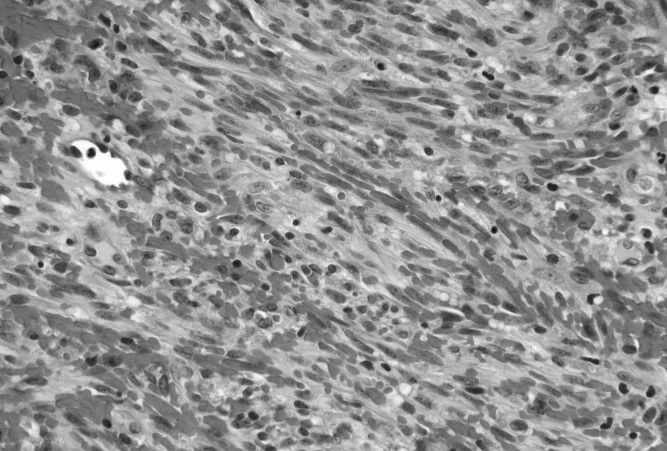

Sarcoma

Sarcomas are cancers that form in bones and connective tissues including muscle, fat, blood vessels, lymph vessels, tendons and ligaments.